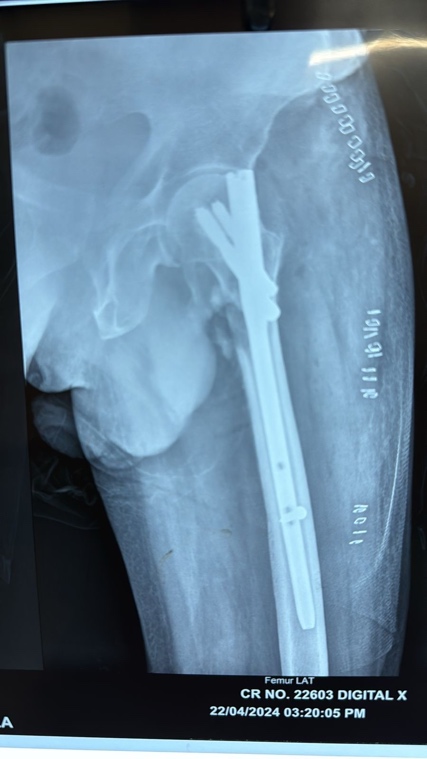

Fig. 8: Post op x-rays

Fig. 9: Post op X-rays

Fig. 10: Post op X-rays (2nd)

Upon completion of cement insertion, the appropriately sized screw was inserted without any time delay following insertion of cement, followed by derotation screw (fig. 6,7). In none of the case we notices loss of reduction and fixation during whole of the process. The nail was statically locked distally with one screw. Postoperative management included standard prophylaxis for deep vein thrombosis, and patients were mobilised with weight-bearing as tolerated and no cement related complications were noted.